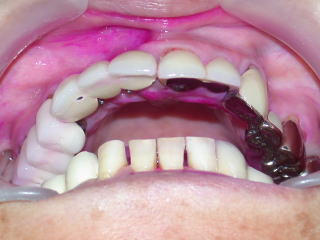

症例9:50歳代女性(新潟県長岡市要町 要町歯科 インプラント)

右上1、2、3が義歯ですが、見た目、装着感、発音など色々の不満があり、インプラントを希望しています。

こちらの患者さんは下顎両側臼歯部にもインプラントを入れており、インプラントの良い点をご自身で感じています。